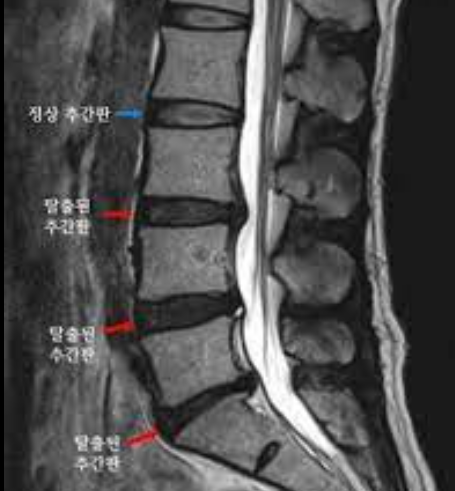

추간판 탈출증은 탈장의 일종으로 추간판의 일부가 피막을 찢고 탈출한 상태로 흔히 ‘디스크’라고 한다.

추간판을 디스크라고 부르기에 이 병이 난 부위의 이름을 붙여 만약 허리에 났다면 ‘허리 디스크’, 목에 났다면 ‘목 디스크’라고 부른다.